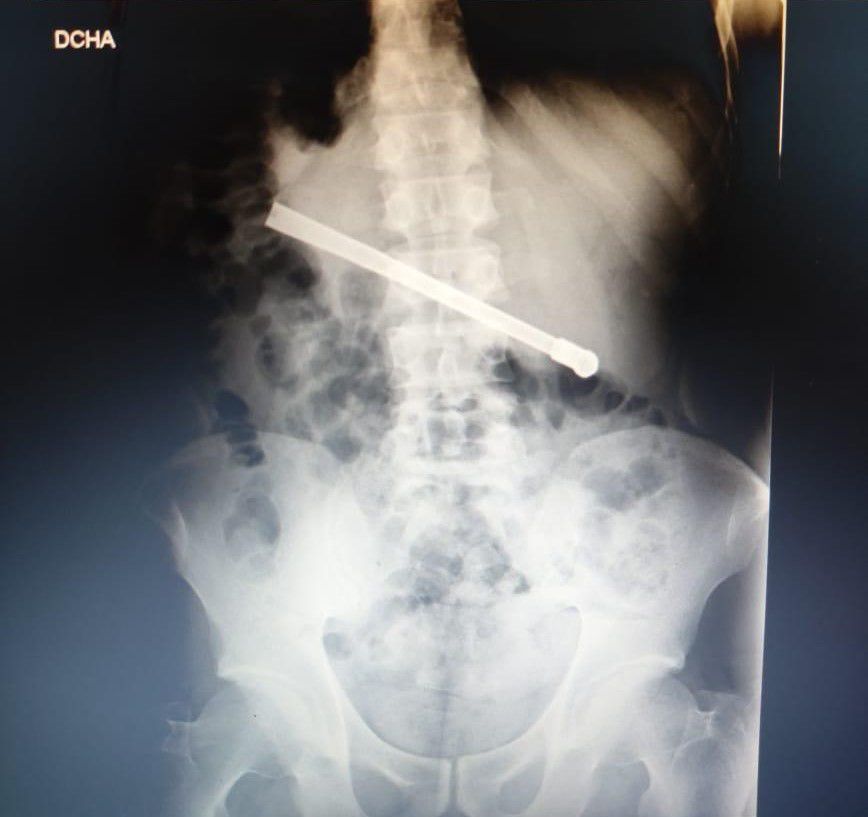

El episodio comenzó en la noche del domingo, cuando el detenido pidió asistencia médica por un fuerte dolor estomacal. Tras ser trasladado al servicio médico del penal y, posteriormente, a la Unidad Penitenciaria de 27 de Febrero al 7800, se le realizó una radiografía que reveló la presencia del objeto metálico, alojado transversalmente en la cavidad torácica.

Por la gravedad del caso, el hombre fue derivado al hospital Eva Perón, donde permaneció internado y fue operado con éxito en la tarde del lunes. Actualmente se encuentra en observación y, una vez recuperado, regresará al CPR.